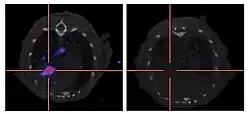

Addition of the sodium-iodide symporter (NIS) gene to the viral genome causes infected tumour cells to express NIS and accumulate iodine. When combined with radioiodine therapy it allows local radiotherapy of the tumour, as used to treat thyroid cancer. The radioiodine can also be used to visualise viral replication within the body by the use of a gamma camera.[89] This approach has been used successfully preclinically with adenovirus, measles virus and vaccinia virus.[96][97][98]

- ^ a b c Haddad D, Chen CH, Carlin S, Silberhumer G, Chen NG, Zhang Q, Longo V, Carpenter SG, Mittra A, Carson J, Au J, Gonen M, Zanzonico PB, Szalay AA, Fong Y (2012). Gelovani JG (ed.). "Imaging characteristics, tissue distribution, and spread of a novel oncolytic vaccinia virus carrying the human sodium iodide symporter". PLOS ONE. 7 (8): e41647. Bibcode:2012PLoSO...741647H. doi:10.1371/journal.pone.0041647. PMC 3422353. PMID 22912675.